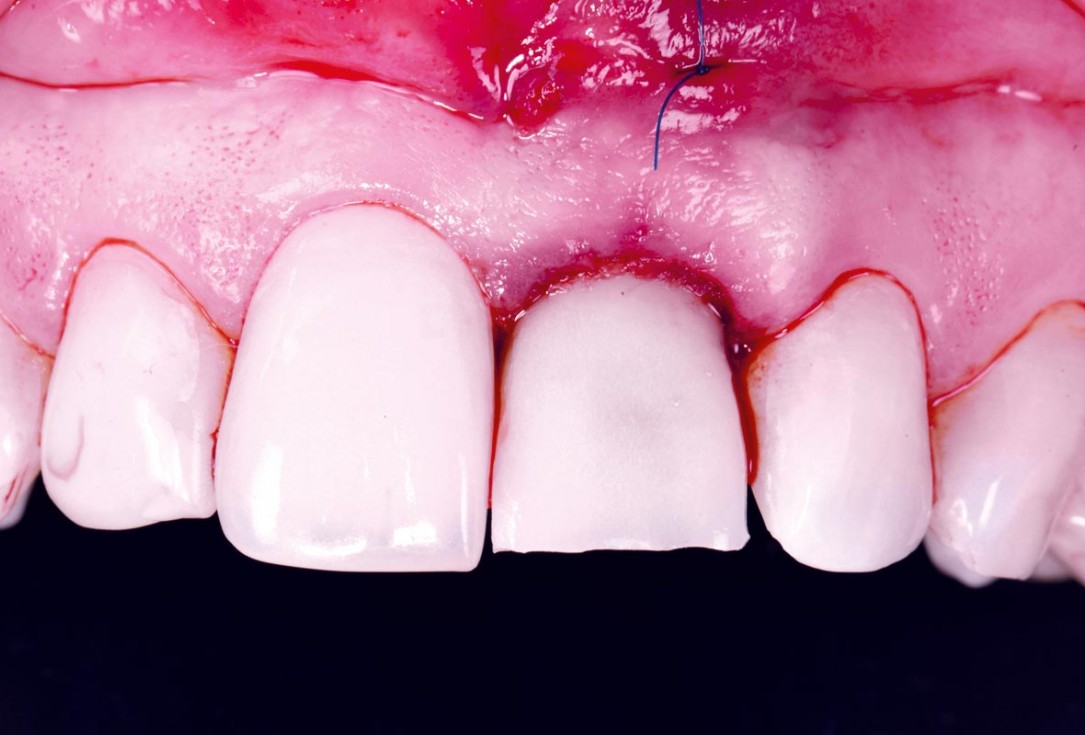

25/30 - Immediate temporary in placeExcellent aesthetic result of buccal augmentation with mucoderm® and maxgraft® after immediate implant placement - 3-years follow-up - Dr. A. Puišys

-